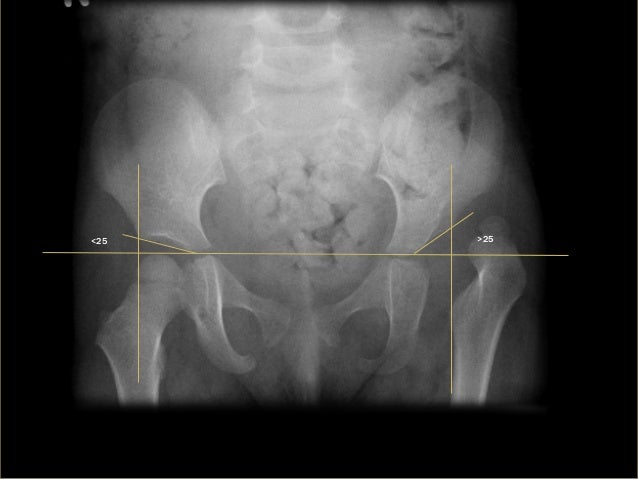

M16.0 is a billable diagnosis code used to specify a medical diagnosis of bilateral primary osteoarthritis of hip. The code M16.0 is valid during the fiscal year 2021 from October 01, 2020 through September 30, 2021 for the submission of HIPAA-covered transactions.#N#The ICD-10-CM code M16.0 might also be used to specify conditions or terms like osteoarthritis of bilateral hip joints, osteoarthritis of left hip joint, osteoarthritis of right hip joint or primary coxarthrosis, bilateral.#N#The code is commonly used in orthopedics medical specialties to specify clinical concepts such as osteoarthritis of the hip.

The General Equivalency Mapping (GEM) crosswalk indicates an approximate mapping between the ICD-10 code M16.0 its ICD-9 equivalent. The approximate mapping means there is not an exact match between the ICD-10 code and the ICD-9 code and the mapped code is not a precise representation of the original code.

The ICD code M16 is used to code Osteoarthritis. Osteoarthritis (OA) is a type of joint disease that results from breakdown of joint cartilage and underlying bone. The most common symptoms are joint pain and stiffness. Initially, symptoms may occur only following exercise, but over time may become constant.

Osteoarthritis (OA) is a type of joint disease that results from breakdown of joint cartilage and underlying bone. The most common symptoms are joint pain and stiffness. Initially, symptoms may occur only following exercise, but over time may become constant. Other symptoms may include joint swelling, decreased range of motion, and when the back is affected weakness or numbness of the arms and legs. The most commonly involved joints are those near the ends of the fingers, at the base of the thumb, neck, lower back, knees, and hips. Joints on one side of the body are often more affected than those on the other. Usually the problems come on over years. It can affect work and normal daily activities. Unlike other types of arthritis, only the joints are typically affected.